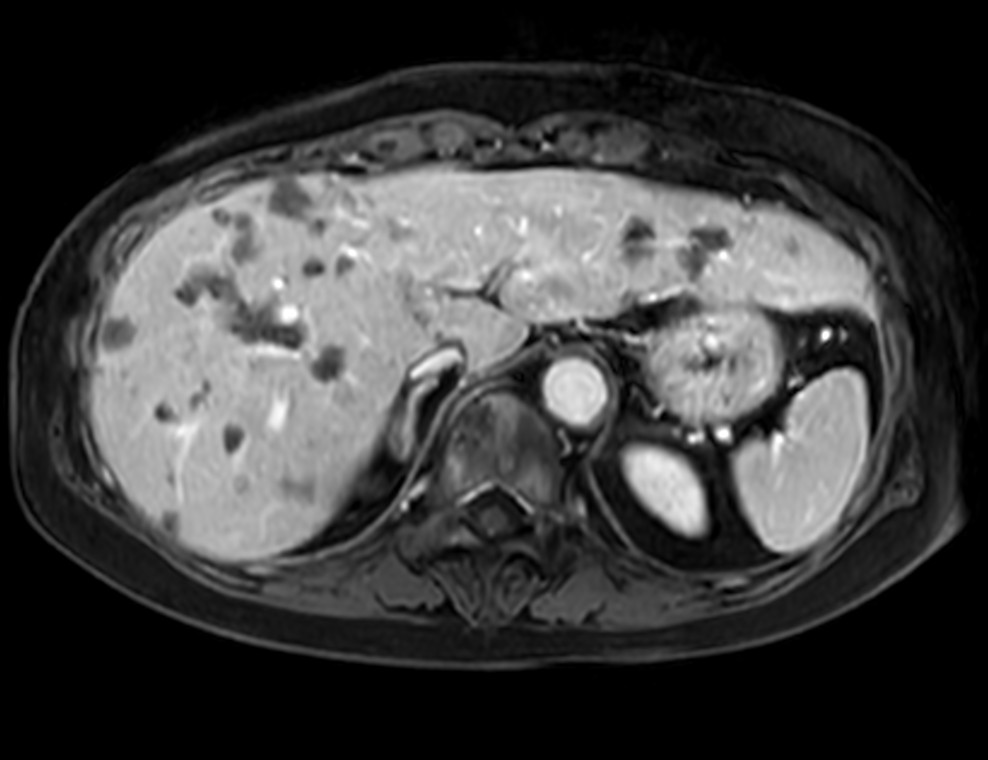

Axial Dynamic eTHRIVE

Axial eTHRIVE 90 sec Post gado

Axial eTHRIVE 2 min Post gado

Axial eTHRIVE 3 min Post gado

Axial eTHRIVE 15 min Post gado